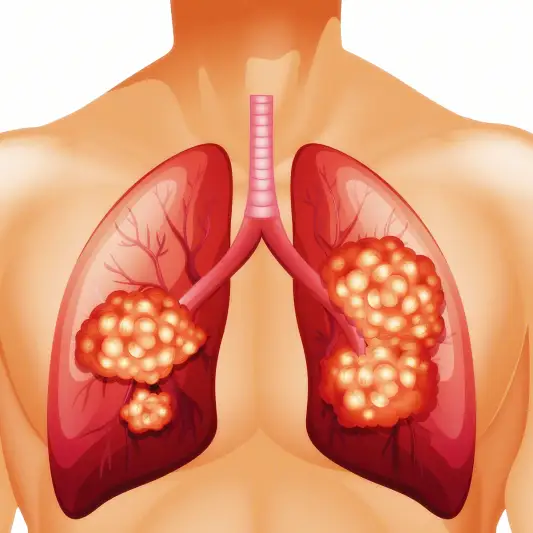

폐암 수술은 환자들에게 중대한 물리적 및 정신적 영향을 미칩니다. 수술 후 이러한 영향을 완화하고 성공적인 회복을 위해서는 알맞은 관리와 후송 기간이 필요합니다.

폐암 환자와 그 가족들에게는 적절한 관리 및 후송 기간의 중요성에 대해 충분히 알려주는 것이 필요합니다. 폐암 수술 후의 회복은 어려울 수 있지만, 적절한 지원과 돌봄을 받으면 삶의 질을 크게 향상시킬 수 있습니다. 따라서, 폐암 수술 환자들은 반드시 의사와 함께 적절한 관리 및 후송 계획을 수립해야 합니다.